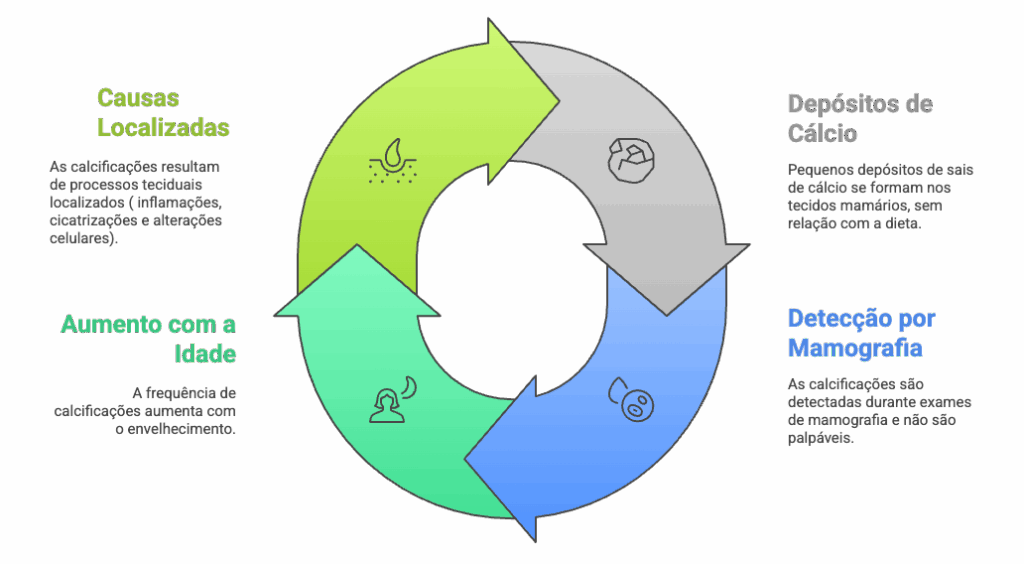

Imagine pequenos pontinhos brancos, como grãos de areia, que aparecem na imagem da sua mamografia. Essas são as calcificações mamárias: minúsculos depósitos de sais de cálcio que se formam nos tecidos da mama.

- Não são visíveis a olho nu nem sentidas no autoexame: Sua detecção acontece quase exclusivamente pela mamografia.

- São extremamente comuns: A frequência aumenta naturalmente com o passar da idade, especialmente após a menopausa, como parte do processo de envelhecimento natural do tecido mamário.

- Não têm relação com a sua dieta: O surgimento de calcificações não é causado pelo consumo de alimentos ricos em cálcio ou por suplementos. É um processo localizado, uma resposta do próprio tecido a diversas situações, como inflamações passadas, cicatrizações ou alterações celulares.